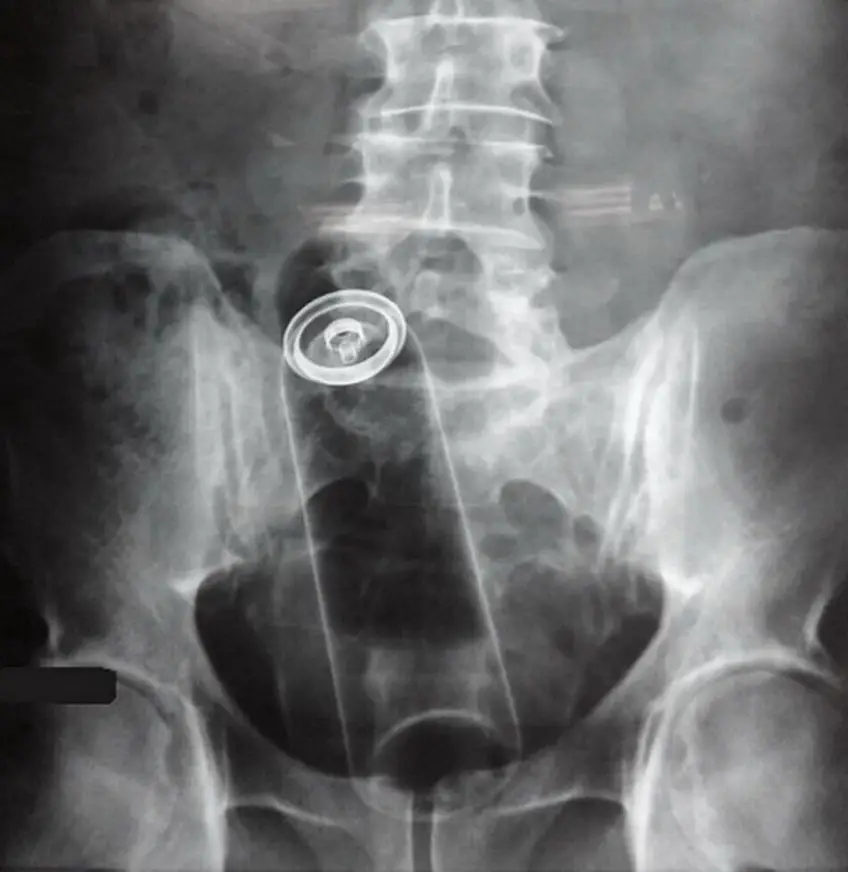

MEDICINA ONLINE OGGETTI CORPO ESTRENEO ANO BAMBINO ESOFAGO STOMACO BATTERIE SEX TOYS OGGETTI SESSO GIOCATTOLI TOSSICI BOTTIGLIA PENNA PENNARELLO COLON RETTO RISCHI COSA FARE COLONSCOPIA

Published 18/04/2018 at 1016 × 1045 in Corpi estranei nel tratto digerente: rischi e cosa fare in bambini e adulti

MEDICINA ONLINE OGGETTI CORPO ESTRENEO ANO BAMBINO ESOFAGO STOMACO BATTERIE SEX TOYS OGGETTI SESSO GIOCATTOLI TOSSICI BOTTIGLIA PENNA PENNARELLO COLON RETTO RISCHI COSA FARE COLONSCOPIA INTESTINO DIGERENTE RX RADIOGRAFIA